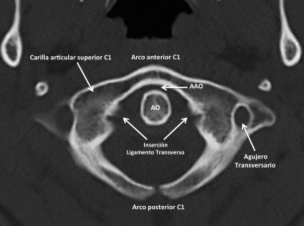

Luego encontramos a C1 formada por un arco anterior y otro posterior con sus masas laterales donde se ubican las superficies articulares que articulan con los CO y con C2 (►Fig. 2). Por último se suma C2 que contribuye con superficies articulares ubicadas en la cara superior de sus sectores laterales y en la apófisis odontoidea (AO) (►Fig. 3).

TCMD, corte axial, ventana ósea, C1. Vista axial de C1 con sus distintos sectores anatómicos y relaciones principales. Abreviaciones: AAO, articulación atloido-odontoidea; AO, apófisis odontoidea de C2.